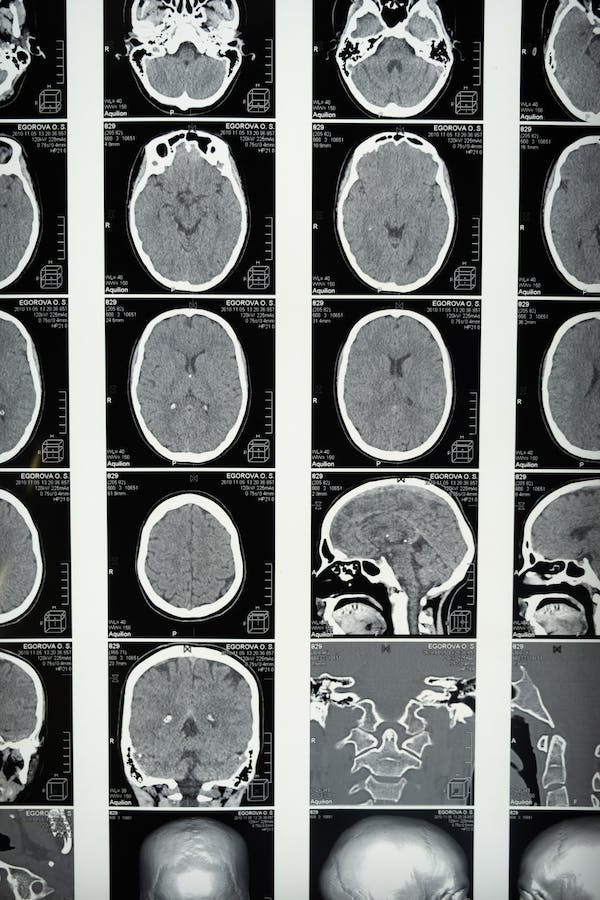

Los estudios de imágenes cerebrales sugieren que la obesidad se asocia con atrofia neural. Se han informado alteraciones estructurales en la arquitectura neural de personas con obesidad. Por ejemplo, un índice de masa corporal elevado se relaciona con una disminución del volumen cerebral, independientemente de la edad y las comorbilidades. Además, un IMC elevado está asociado con la atrofia de la materia gris en las regiones temporales, frontales y occipitales.

En adición, se presentan efectos similares en el hipocampo, el tálamo y el mesencéfalo. No menos importante, se ha documentado una disminución de la integridad de la materia blanca en todo el cerebro.

Además de las alteraciones estructurales y morfológicas en el cerebro de las personas con obesidad, los estudios de imágenes cerebrales muestran una actividad funcional alterada. Lo anterior incluye una disminución del flujo sanguíneo regional hacia la corteza prefrontal en adultos sanos con un IMC elevado.

También, se ha observado una reducción significativa de la actividad funcional en áreas corticales asociadas con la memoria episódica, como el giro angular y la corteza prefrontal dorsolateral, en personas con obesidad y resistencia a la insulina. Así, las personas con obesidad muestran una menor activación relacionada con tareas de memoria de trabajo en la corteza parietal derecha (Dye et al., 2017).

La obesidad se asocia con un aumento de la “edad cerebral” en lo que respecta a la atrofia de la materia blanca cerebral. La mayor atrofia se identifica en la mediana edad, lo que equivale a un aumento estimado de 10 años en la edad cerebral.